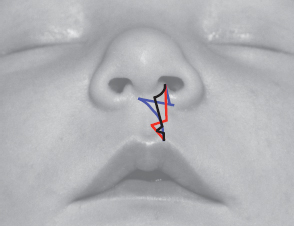

45 ○ The goal of the anatomic subunit approximation technique is to bring the medial and lateral lip elements together along the seams of anatomic subunits. ○ The anatomic subunit approximation technique is a modification of the Rose and Thompson repairs. In most cases it also incorporates a modification of the inferior triangle repair. ○ At the height of the lip, closure points in the nostril sill are chosen to achieve: – Nostril margins of equal circumference – Alar base symmetry from the anterior view ○ The noncleft side Cupid’s bow peak should be designed where the upward concavity of the bow meets the upward convexity of the lateral lip element. No corresponding upward convexity exists on the cleft side of the medial lip element. This convexity must come from the cleft side lateral lip lateral to Noordhoff’s point. ○ Medial and lateral lip roll elements approximate in an end-to-end fashion such that the subunit of the roll is not interrupted by a complex scar. ○ Tension of the repair is optimally positioned above the roll, thus accentuating the pout of the lip. ○ An inferior triangle is used when required. ○ Lateral lip element markings vary to accommodate the vertical height of the lateral lip element. ○ Noordhoff’s point should not be compromised. Lateral lip element transverse length need not be sacrificed to achieve vertical height. ○ The anatomic subunit approximation technique can be used in all cases of unilateral cleft lip. Dr. Samuel Noordhoff of the Chang Gung Memorial Hospital in Taipei, Taiwan, used a modification of Millard’s rotation-advancement repair; Dr. Hugh Thomson, at the Hospital for Sick Children in Toronto, Canada, performed a modification of the Randall-Tennison inferior triangle repair.1–6 Both of these highly skilled surgeons were able to achieve wonderful results, but there are drawbacks to each technique. Common to both of these repairs is the principle of medial lip element elongation using tissue from the lateral lip element. By incorporating the Rose-Thompson principle, achieving length by the approximation of curved or angled lines, the amount of tissue borrowed from the lateral lip can be reduced. Burget and Menick7 contributed the concept of anatomic subunits as it applies to nasal reconstruction. Other influences have probably contributed to the anatomic subunit approximation technique as well.8 Rotation-advancement repairs are “cut-as-you-go” techniques. If the original rotation incision is inadequate to achieve a balanced Cupid’s bow, the surgeon is obliged to consider a back-cut, which introduces additional scar and lowers the transverse limb of the repair. Similarly, if the leading edge of the advancement incision is too short, because the vertical height of the lateral lip element is short (often the case in complete clefts), length must be gained at the expense of lateral lip element transverse length. These maneuvers should be considered compromises. In contrast, the anatomic subunit approximation technique requires the surgeon to commit to a plan before incisions are made to achieve the end goals of balance, preservation of key landmarks, and respect for anatomic subunits. If carried out in the proper sequence, checkpoints along the way allow for evaluation and modification of the original plan to ensure that these goals are met. The anatomic subunit approximation technique is a modification of the Rose9 and Thompson10 repairs. In many cases it is also a modified inferior triangle repair. In contrast to the Thompson repair, the angles are positioned just above the cutaneous roll elements of the medial and lateral lip elements. The straight line repairs of Rose and Thompson have been further modified so as to ascend the lip along a line symmetrical with the noncleft-side philtral column and then ascend superolaterally, bordering the lip-columella junction, to the point of closure in the nostril sill. In minor clefts, the Rose-Thompson principle is sufficient. For most patients with more significant canting of the Cupid’s bow, a small triangle is also positioned above the cutaneous roll. The lengthening achieved by the Rose-Thompson effect significantly reduces the size of the inferior triangle compared with a typical inferior triangle repair. Noordhoff’s vermilion triangular flap is used to correct any vermilion height deficiency of the medial lip element. The repair respects and retains all key landmarks and produces a cutaneous scar positioned along the seams of anatomic subunits. The tension of the repair is positioned above the roll. This accentuates the pout of the lip and allows for the roll elements to approximate end-to-end so the subunit of the roll is not interrupted. At first glance, the anatomic subunit approximation technique may appear to involve the excision of excessive cleft marginal tissue. However, the repair produces a scar in the upper half of the lip that lies intermediate in position to those produced by the rotation-advancement repair and the inferior triangle repair (Fig. 45-1). The scar of the inferior triangle repair is more lateral in the upper part of the lip, indicating that more lateral lip skin is discarded with this repair. Fig. 45-1 The anatomic subunit approximation technique produces a scar in the upper half of the lip that lies intermediate in position to those produced by the rotation-advancement repair and the inferior triangle repair. The rotation-advancement repair, on the other hand, discards more medial lip in the form of the C-flap, which is truly discarded in many incomplete cleft repairs and is displaced from the lip into the sill in complete cleft repairs. Further discard of valuable red lip occurs when lateral lip transverse length is sacrificed to achieve vertical height when the lateral lip element is vertically short. Medial and lateral lip elements thus share more equally in the discard of cleft marginal tissues in the anatomic subunit approximation technique. Furthermore, Noordhoff’s point, and therefore transverse lateral lip element length, is never compromised to achieve vertical height. All patients with unilateral cleft lip are candidates for the anatomic subunit approximation technique. The vertical limb (greater height) of the repair will vary in slope to mirror the noncleft-side philtral column. With minor clefts, the inferior triangle above the cutaneous roll may not be required. Lateral lip markings will vary depending on the vertical height of the lateral lip element. Patients with a contralateral minor-form cleft should be considered for a synchronous bilateral cleft lip repair. This approach provides the best opportunity to achieve symmetry of the Cupid’s bow and of the resultant scar, and provides the ideal opportunity for reconstruction of the prolabial deficiencies of the cutaneous roll, vermilion, and median tubercle.11 For patients with complete clefts, the treatment algorithm in Table 45-1 can be applied. I believe the greatest benefit of presurgical orthodontics used to improve the alignment of the alveolar arches is the increased symmetry of the skeletal nasal base. This is particularly beneficial when significant discrepancy exists in the anteroposterior positions of the alar bases. The anatomic subunit approximation technique can be performed if presurgical orthodontics have not been used. Lip adhesion is not required. Table 45-1 Treatment Algorithm for Patients With Complete Clefts M&T, Myringotomy and ventilation tubes; NAM, nasoalveolar molding; VPI, velopharyngeal insufficiency. Diagrams for this chapter are simplified relative to the original description; the numerical descriptions of the points are described in the text (Fig. 45-2). At the height of the lip, within the nostril sill, two points are chosen: the medial point of closure in the nostril sill (point 16) and the lateral point of closure in the nostril sill (point 19) (Fig. 45-3, A). These points are not distinct anatomic points and as such are the most difficult to describe. The medial point of closure in the nostril sill is positioned lateral to the curve of the lip columellar crease. It will be positioned more medially in complete clefts and more laterally in incomplete clefts. The lateral point of closure in the nostril sill is then chosen on the lateral lip element, relative to the medial point of closure in the nostril sill such that when these two points approximate, two goals are accomplished: (1) nares of equal circumference and (2) symmetry of the alar bases from the anterior view. This is confirmed by manipulation of the medial and lateral lip elements. If the lateral lip is sufficiently tethered and the medial and lateral lip elements cannot be brought together, the lateral lip element should be released first. In the same patient, it would be possible to choose these two points differently and still succeed. These points do not represent true anatomic points; rather they are two points relative to one another such that when they approximate they achieve the previously mentioned goals. Along the vermilion-cutaneous junction, the midline (point 4) and the noncleft-side Cupid’s bow peak (point 5) are marked (Fig. 45-3, B). The noncleft-side Cupid’s bow peak is not marked at the highest point of the curve of the lip. It is marked where the straight portion of the noncleft-side half bow meets the convexity of the lateral lip element. No such convexity occurs on the cleft side of the medial lip element. This curve of the bow on the cleft side will come from the lateral lip element lateral to Noordhoff’s point. The cleft-side peak of the Cupid’s bow (point 6) is positioned on the vermilion-cutaneous junction on the cleft side of the medial lip element equidistant from the midline (point 4). Fig. 45-2 Left unilateral complete cleft lip. A, Preoperative appearance. B and C, Presurgical markings. Fig. 45-3 Left unilateral complete cleft lip medial lip presurgical markings. A, At the height of the lip, within the nostril sill, two points are chosen. The medial point of closure in the nostril sill (point 16 on Fig. 45-2, C) is positioned lateral to the curve of the lip-columellar crease. The lateral point of closure in the nostril sill (point 19 on Fig. 45-2, C) is then chosen on the lateral lip element, relative to the medial point of closure in the nostril sill such that when they approximate, the nares are of equal circumference and the alar bases are symmetrical from the anterior view. B, The noncleft-side Cupid’s bow peak (point 5 on Fig. 45-2, C) is marked where the straight portion of the noncleft-side half bow meets the convexity of the lateral lip element. No such convexity occurs on the cleft side of the medial lip element. This curve of the bow on the cleft side will come from the lateral lip element lateral to Noordhoff’s point. Fig. 45-4 The base width of the inferior triangle (c) is calculated. The total lip height (a; line 2-7 on Fig. 45-2) and greater lip height (b; line 3-8 on Fig. 45-2) are measured from points just above the cutaneous roll above the peaks of the Cupid’s bow to the height of the philtral column in the lip-columellar crease. Approximately 1 mm of lengthening occurs by a Rose-Thompson effect, thereby reducing the required size of the inferior triangle. Along a line perpendicular to the vermilion-cutaneous junction and passing through the cleft-side peak of the Cupid’s bow, point 8 is marked just above the cutaneous roll (at the junction between the cutaneous roll and the “flat” portion of the upper lip). Caudally, from point 8 along this line the incision line will continue across the free border of the lip into the mucosa. From point 8, the incision line will ascend the lip along a line symmetrical with the noncleft-side philtral column to the level of the lip-columellar crease. From the height of the philtral column (point 3), the incision line will traverse superolaterally just outside the lip-columellar crease to the medial point of closure in the nostril sill (point 16). Measurements are taken from the heights of the philtral columns at the lip-columellar crease to the points marked above the peaks of the Cupid’s bow above the cutaneous roll (Fig. 45-4). The total lip height is measured with the lip at rest. The greater lip height is measured with gentle downward traction on the lip to unfurl the medial lip and predict the tension on the lip after repair. The lesser lip height (base width of the small inferior triangle) is equal to the total lip height minus the greater lip height and less 1 mm: